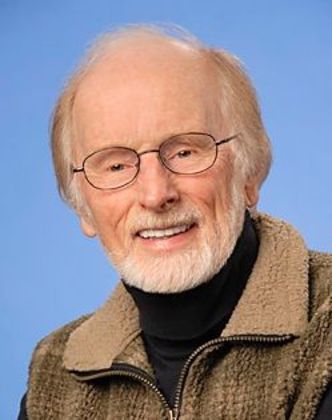

Full Mouth Rehabilitation: Tim

This healthcare professional had been wearing a removable appliance for years. He had a deep overbite and the anchor teeth for his appliance were breaking down. His main concern was to restore the functionality of his teeth with a fixed, long term solution.